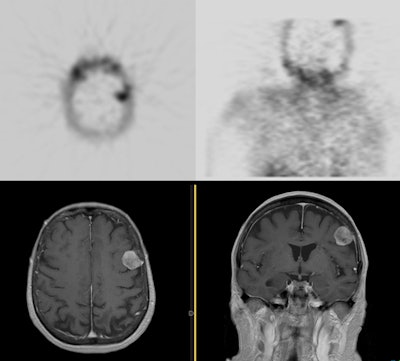

Meningioma on sestamibi parathyroid scan: A Tc-MIBI exam demonstrated a focal area of tracer uptake in the left parietal lobe of the brain. This area was not included on the planar images. As sestamibi is also a tumor agent, a MRI of the rbain was performed and demonstrated a meningioma corresponding to the area of tracer uptake. Click here to view a cine loop of the SPECT MIP images |